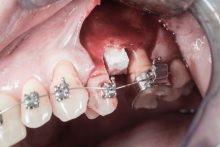

Procedury te są stosowane w sytuacji niedostatecznej ilości kości, skutkującej odsłonięciem gwintu, podczas gdy wszczepiamy implanty stomatologiczne lub też jako zabiegi poprzedzające ich wprowadzenie.​

To kolejna metoda umożliwiająca precyzyjną odbudowę zadanego kształtu tkanki kostnej przy użyciu standardowych materiałów kościotwórczych, kości własnej lub PRF oraz zewnętrznego rusztowania w postaci siatki z biozgodnego stopu tytanu. Siatka jest indywidualnie projektowana w technologii CAD CAM i następnie drukowana dla konkretnego przypadku.

Siatki stanowią stabilną obudowę – ograniczenie nadające kształt regenerowanej kości przy użyciu upakowanego pod nią materiału. Utrzymują i stabilizują rozdrobniony granulat kościotwórczy, co jest warunkiem prawidłowego procesu gojenia, jednocześnie nadając anatomiczny kształt i zakres odbudowie kostnej sprzed jej zaniku.

Ten rodzaj odbudowy kostnej stosowany jest w sytuacjach złożonych, trójwymiarowych 3D ubytków kości, przy których standardowe metody odbudowy są niewystarczające. Ilość kości, którą możemy uzyskać, stosując tę metodę, to nawet kilka centymetrów sześciennych.

Metoda rekonstrukcji kostnej w oparciu o indywidualnie drukowane siatki z tytanu dla implantacji wszczepów śródkostnych stosowana jest najczęściej jako dwuetapowa. W pierwszym etapie odbudowywana jest kość, natomiast implanty wszczepiane są po okresie 4–6 miesięcy. Na wgojenie implantów oczekujemy od 4 do 6 miesięcy w zależności od miejsca ich lokalizacji. Siatka tytanowa po spełnieniu swojej funkcji rusztowania dla odbudowującej się kości jest następnie usuwana w dniu wszczepienia implantu. Jeżeli kość spełnia odpowiednie warunki, istnieje możliwość zastosowania modyfikacji siatki tytanowej, która umożliwia jednoczesne wprowadzenie implantów wraz z odbudową kostną. Wariant ten skraca czas od pierwszego zabiegu do wykonania gotowych koron protetycznych na wprowadzonych implantach.